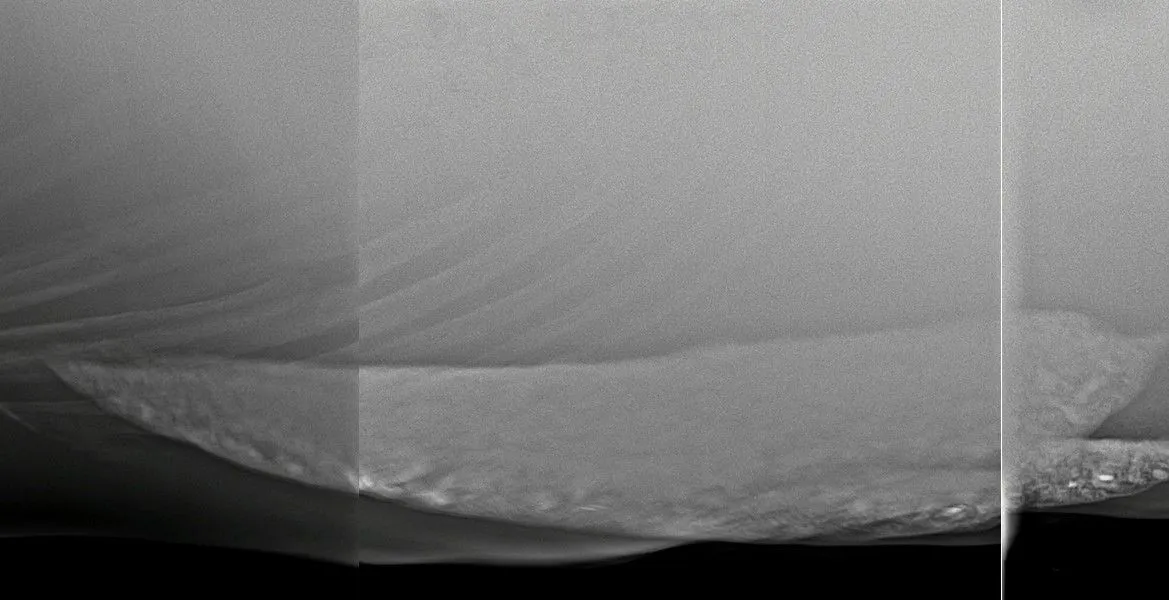

You may commonly see your veterinarian auscultate your horse for sand (listen to its abdomen with a stethoscope). When sand is moving within the digestive system, it sounds like ‘waves on the beach’, which is what we are listening for! It is important to note, however, that auscultation can only confirm if sand is present and cannot be used to completely rule out the presence of sand. We have seen many cases where no sand is auscultated; however, we know the horses are full of sand, and it has been confirmed on radiographs.

The best way to diagnose sand is abdominal radiographs, which can confirm the presence of sand and also the quantity of sand. These can be performed at your dental appointment, please just let us know at your appointment.

This information can then be used to formulate an appropriate treatment plan. Before-and-after radiographs can also help determine the success of a treatment plan and ensure the sand has actually been removed.